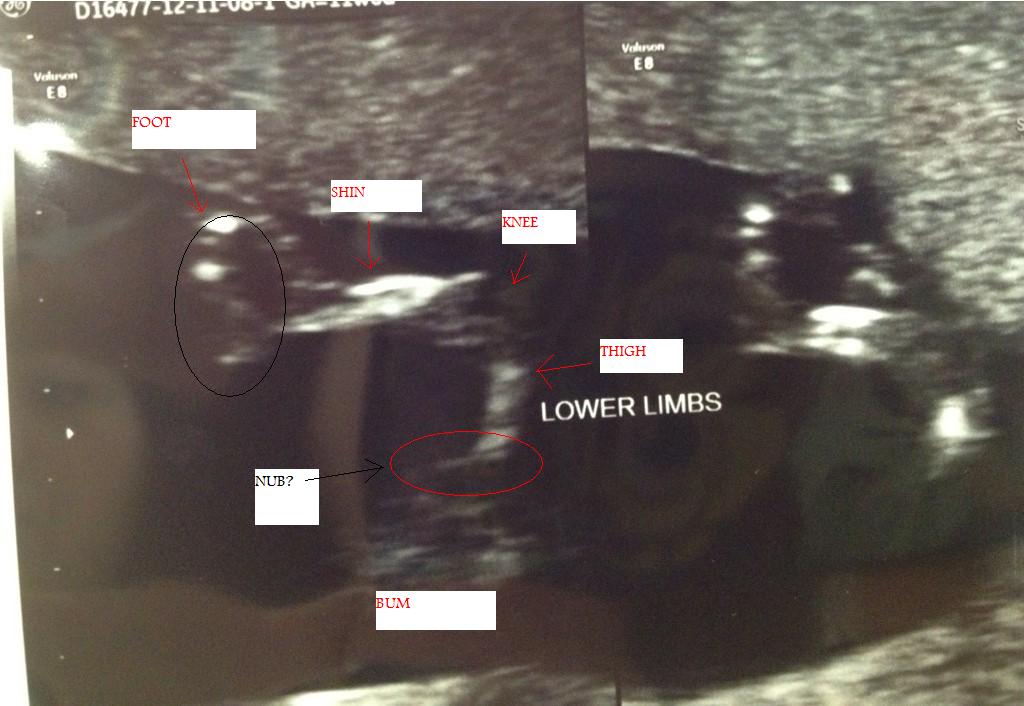

Hi girls, here is a pic that I think might be nub? The tech refused to give me any potty shots or nub shots but I think this one might show it?

Have a couple more and will post later but I think this is the clearest. Would love to know your guesses please :)